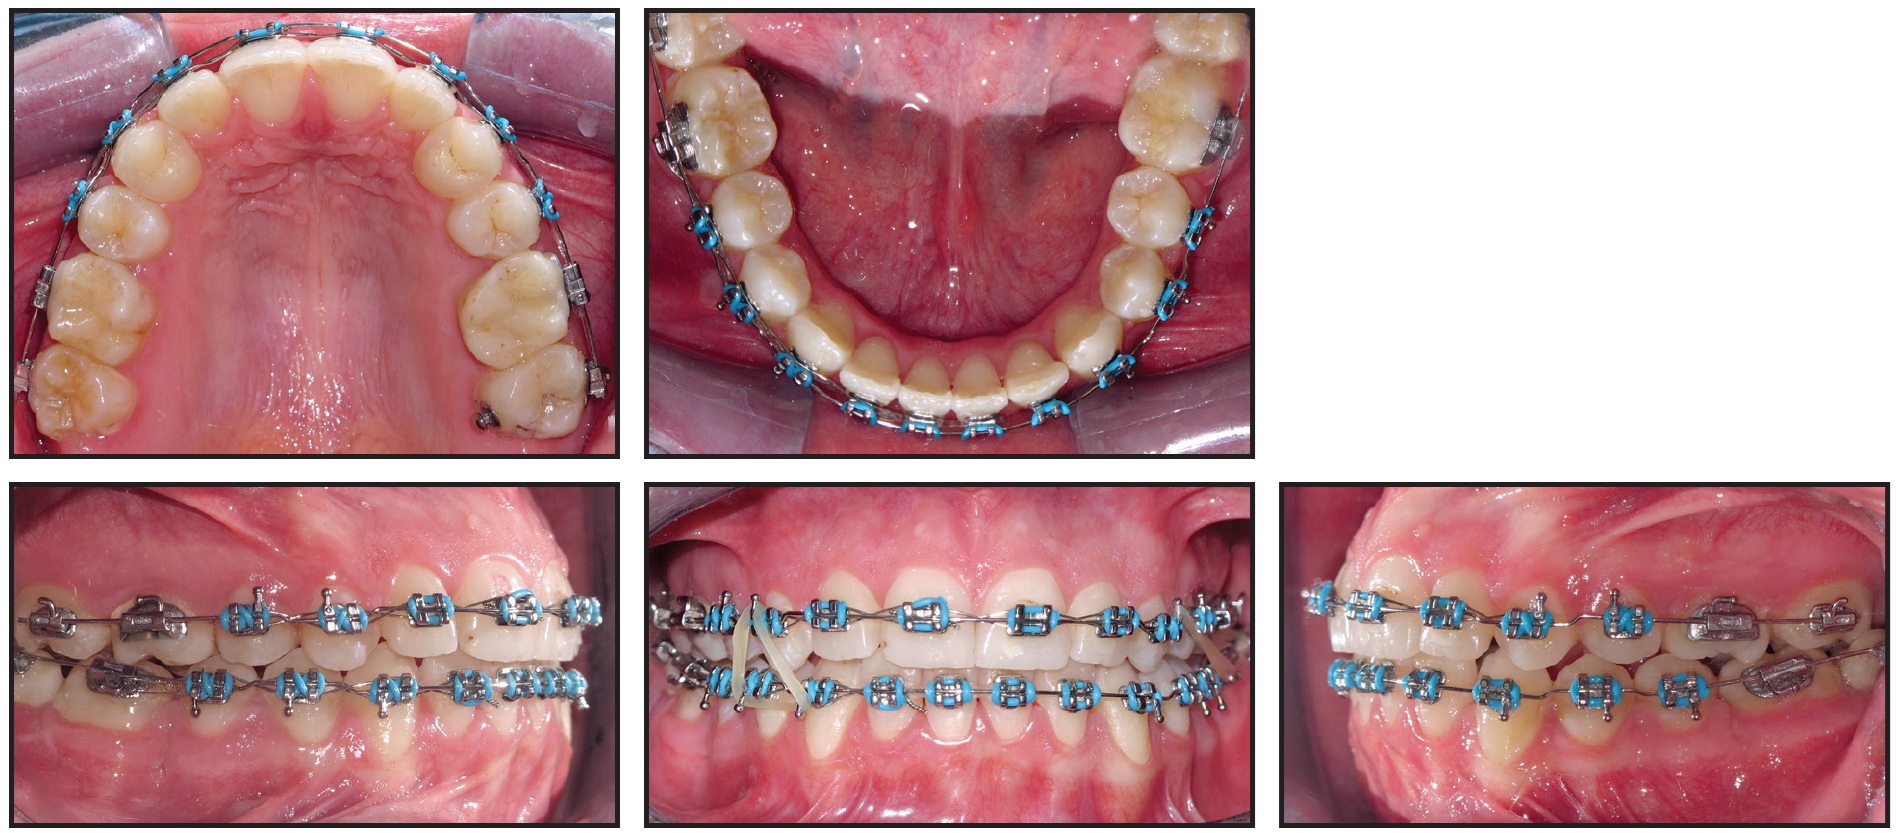

Retraction mechanics were applied to distalize the lower buccal segments and protract the second molars (Fig. 6). Three months later, the lower premolars and canines had been retracted enough to relieve the anterior crowding and allow anterior alignment without proclination (Fig. 7).

Fig. 6 Retraction mechanics applied to distalize lower buccal segments and protract second molars.

Fig. 7 Three months later, lower anterior teeth bonded and space closure initiated in upper arch.

Space closure was started simultaneously in the upper arch. Five months later, leveling and alignment of the lower arch were completed on an .019" × .025" stainless steel archwire.